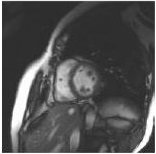

4. View resulting short axis image.

Figure 4. Short axis view